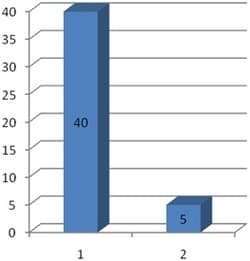

The high initial value was 34. This dropped to 2 after using the Aires Defender for 3 hours 40 minutes.

The high initial value of 40 indicates the possibility of developing serious diseases.

After 4 hours of using the Aires Defender, the value was decreased to 5.